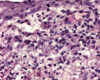

Pemphigus foliaceus (PF) is the most common autoimmune skin disease in dogs and cats.